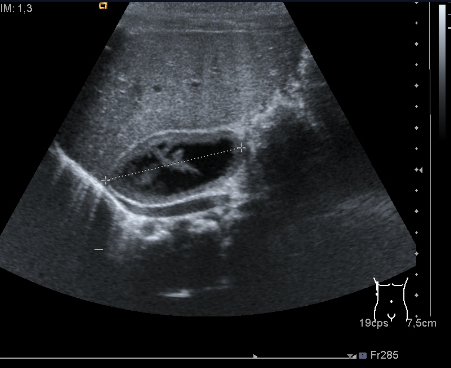

En el neonato, la masa suprarrenal más frecuente es el sangrado, casi el 75% de los sucesos patológicos en este órgano en la edad neonatal es debido a estos procesos. Suelen ser asintomáticas. Ecográficamente esta figura patológica se observa más habitualmente en el lado derecho y se comporta con estas características:

1. Aspecto quístico

2. Ausencia de la señal Doppler

El punto número dos es clave, por que en el diagnóstico diferencial con la otra gran figura patológica de la glándula a nivel suprarrenal en el neonato es el neuroblastoma si bien este tumor usualmente es isoecogénico y con señal Doppler presente.